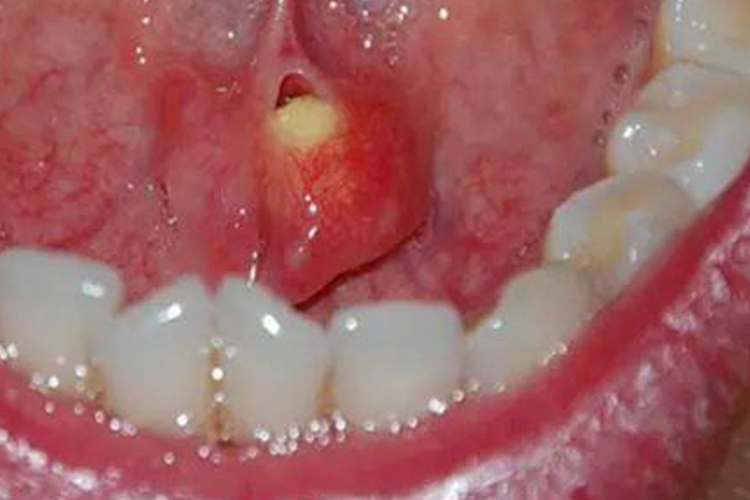

舌下腺和颌下腺结石体积较小时,不会造成唾液腺导管阻塞,通常无任何症状。结石体积较大时,可能会造成导管阻塞,进而引起排唾障碍及继发感染,患者在进食时会出现腺体异常肿大及疼痛。部分患者在进行体格检查时,挤压腺体可见少量脓性分泌物自导管口溢出。若结石体积较大,双手触诊时可触及硬块并伴有压痛。舌下腺和颌下腺结石多在导管内,无法直接看到,偶尔有患者的结节脱出到导管口,多表现为黄白色小颗粒或团块。